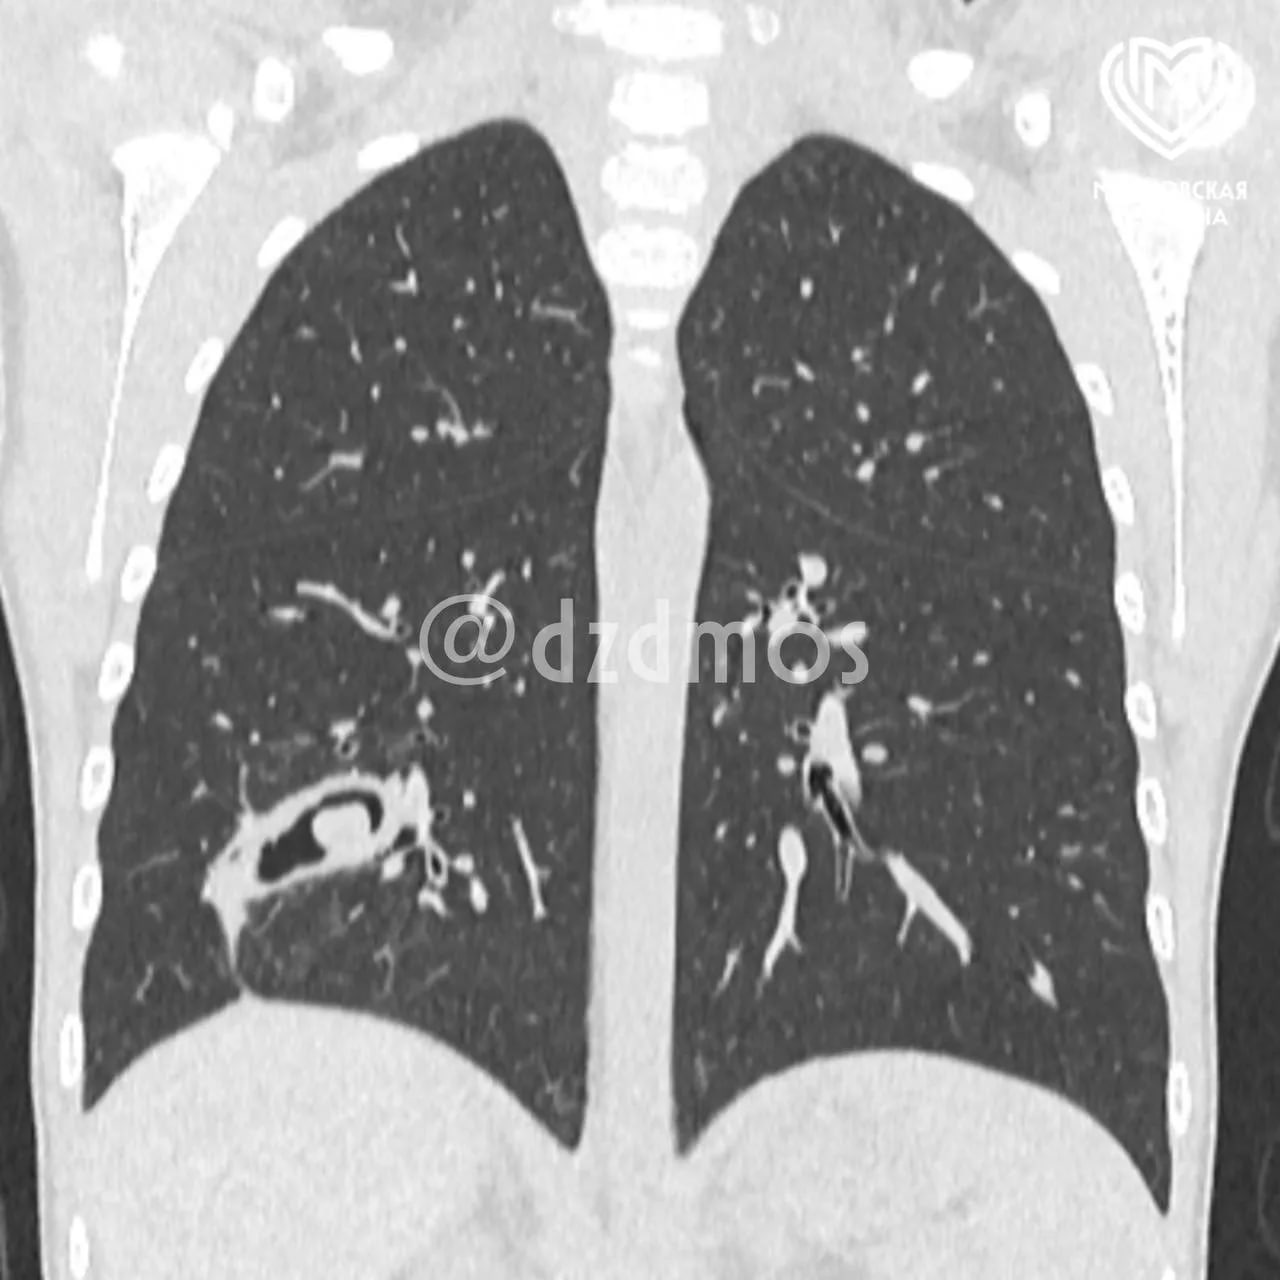

Девочку, которой было тяжело дышать, госпитализировали в больницу в Москве. Застрявшая шелуха впаялась в третий субсегмент правого легкого, сообщили в столичном Департаменте здравоохранения.

"У пациентки образовался бронхоэктаз, то есть плохо функционировали из-за скопления гноя бронхи", рассказал заместитель главного врача по хирургической помощи Дмитрий Еремин.

Московские врачи почистили бронхи от гноя, затем, используя эндоскоп, безопасно захватили скорлупу семечки и вытянули ее из легкого.